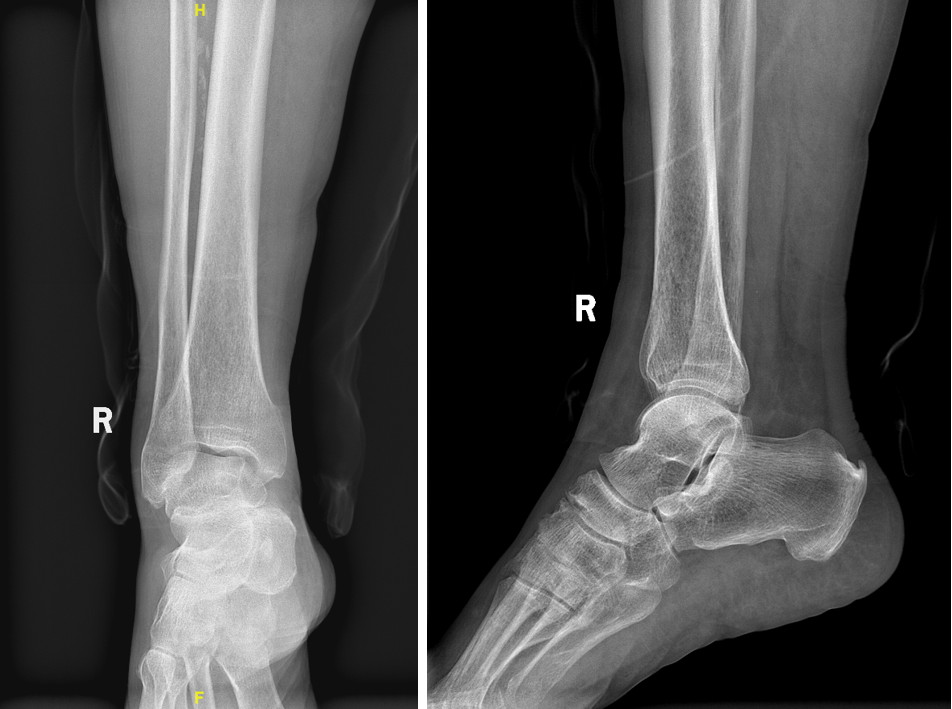

踝關(guān)節(jié)骨關(guān)節(jié)炎關(guān)節(jié)腔注射治療摘要【基本信息】患者男性,69歲【疾病類型】踝關(guān)節(jié)骨關(guān)節(jié)炎,輕-中度,反復(fù)疼痛發(fā)作,伴行走功能障礙【治療醫(yī)院】北京大學(xué)人民醫(yī)院(三甲)【治療方案】踝關(guān)節(jié)腔注射藥物+口服藥物+外用膏藥治療【治療周期】35天【治療效果】明顯改善一、初識(shí)患者患者是一位69歲男性,反復(fù)出現(xiàn)右踝關(guān)節(jié)疼痛10余年,加重伴腫脹、活動(dòng)受限半年,以站立(超過(guò)10分鐘)、走路多了(超過(guò)500米),疼痛明顯,活動(dòng)受限制,同時(shí)出現(xiàn)雙側(cè)踝關(guān)節(jié)腫脹,目前連走路都費(fèi)勁了,由病友介紹,經(jīng)家人陪同坐輪椅來(lái)到我的門(mén)診看病。仔細(xì)詢問(wèn)病史,其實(shí)他的右踝關(guān)節(jié)疼痛不適已經(jīng)有10多年了,年輕的時(shí)候,曾經(jīng)有多次踝關(guān)節(jié)“扭傷”經(jīng)歷,認(rèn)為當(dāng)時(shí)還很年輕,未行休息、就醫(yī)治療,完全靠自行恢復(fù)。最開(kāi)始是下蹲、長(zhǎng)時(shí)間行走、上下樓梯、爬山時(shí)有腳踝周圍有不穩(wěn)定感覺(jué),后出現(xiàn)針刺狀疼痛感覺(jué),后逐漸發(fā)展到走遠(yuǎn)路、活動(dòng)過(guò)量時(shí)踝關(guān)節(jié)酸脹疼痛不適持續(xù)發(fā)作。坐的時(shí)間長(zhǎng)了起身時(shí)也感覺(jué)到疼痛不適,早晨起床時(shí)疼痛癥狀也較為明顯,下午或夜間右踝關(guān)節(jié)酸脹不適較為明顯。查體看他的右踝關(guān)節(jié)輕度的腫脹、外踝處有壓痛點(diǎn),踝關(guān)節(jié)穩(wěn)定性良好,無(wú)明顯變形。右側(cè)踝關(guān)節(jié)皮溫?zé)o升高、皮膚顏色無(wú)發(fā)紅。沒(méi)有痛風(fēng)發(fā)作病史。二、患者治療過(guò)程從他的病史和查體情況來(lái)看,他的右踝關(guān)節(jié)疼痛腫脹可能是“老年踝關(guān)節(jié)骨關(guān)節(jié)炎和關(guān)節(jié)積液慢性持續(xù)期,不排除創(chuàng)傷性踝關(guān)節(jié)炎”,就是踝關(guān)節(jié)骨與軟骨及關(guān)節(jié)囊周圍韌帶、肌腱等因反復(fù)的扭傷、勞累磨損、老化退變等多種因素,在某次受到外界刺激如受涼、活動(dòng)量增加后,引起關(guān)節(jié)急性滑膜炎,然后關(guān)節(jié)積液增多,關(guān)節(jié)腫脹,導(dǎo)致關(guān)節(jié)疼痛、活動(dòng)受限制。但滑膜炎急性發(fā)作時(shí)的踝關(guān)節(jié)腫脹、疼痛,需要與痛風(fēng)性關(guān)節(jié)炎、感染等問(wèn)題相鑒別。為了進(jìn)一步明確判斷,我讓他去拍了一個(gè)踝關(guān)節(jié)X線片,結(jié)果顯示:右踝關(guān)節(jié)對(duì)位可,組成骨邊緣骨質(zhì)增生,關(guān)節(jié)間隙尚可,說(shuō)明右踝關(guān)節(jié)有骨關(guān)節(jié)炎,尚處于輕度至中度階段。踝關(guān)節(jié)正側(cè)位X線片,結(jié)果顯示:右踝關(guān)節(jié)對(duì)位可,組成骨邊緣骨質(zhì)增生,關(guān)節(jié)間隙尚可,說(shuō)明右踝關(guān)節(jié)有骨關(guān)節(jié)炎?所以,針對(duì)他的治療主要是緩解踝關(guān)節(jié)軟骨磨損,滑膜炎所致的關(guān)節(jié)積液引發(fā)的腫脹、疼痛:首先,為了明確排除踝關(guān)節(jié)腔感染,化驗(yàn)抽血:血常規(guī)、大生化、C反應(yīng)蛋白、血沉等,未見(jiàn)尿酸升高,未見(jiàn)白細(xì)胞增多及C反應(yīng)蛋白升高、血沉加快,故患者踝關(guān)節(jié)腔感染風(fēng)險(xiǎn)基本可以排除、痛風(fēng)性關(guān)節(jié)炎也不考慮了;患者目前之所以踝關(guān)節(jié)腫脹、疼痛嚴(yán)重,活動(dòng)受限,主要是因?yàn)橛阴钻P(guān)節(jié)扭傷后,磨損嚴(yán)重,滑膜炎癥,關(guān)節(jié)積液等有關(guān)。其次,行踝關(guān)節(jié)腔玻璃酸鈉穿刺注射治療(1周1次,連續(xù)5次,在第1次和第5次時(shí),聯(lián)合使用利多卡因+得寶松注射),同時(shí),囑咐患者充分休息1個(gè)月,盡量少站少走,尤其是避免爬樓梯,避免下蹲或腳踝部受涼,在平臥情況下進(jìn)行踝關(guān)節(jié)屈伸功能鍛煉(20個(gè)為一組,每天早中晚根據(jù)自己的情況鍛煉各一組,循序漸進(jìn)增加);與此同時(shí),給患者用上非甾體消炎止疼藥、消腫藥(口服)+外用貼劑局部貼敷,以及熱敷理療等綜合方式。三、患者在治療過(guò)程中的注意事項(xiàng)老年輕度-中度踝關(guān)節(jié)骨關(guān)節(jié)炎和關(guān)節(jié)積液慢性持續(xù)期最重要的是休息,盡量少站少走,讓踝關(guān)節(jié)減少承重,一般2周關(guān)節(jié)積液就會(huì)慢慢吸收。但對(duì)于某些踝關(guān)節(jié)腫脹明顯,而又不能明確排除踝關(guān)節(jié)感染、痛風(fēng)的患者,應(yīng)在進(jìn)行踝關(guān)節(jié)腔穿刺注射藥物治療前,給予拍片、肌骨彩超、抽血化驗(yàn)檢查,甚至踝關(guān)節(jié)液穿刺抽液送細(xì)菌培養(yǎng),以明確診斷。這一點(diǎn)非常重要。四、患者的治療效果經(jīng)過(guò)2次踝關(guān)節(jié)腔穿刺得寶松注射治療以及5針踝關(guān)節(jié)腔穿刺注射玻璃酸鈉注射液后(每周1次,共計(jì)5次一個(gè)療程),患者門(mén)診復(fù)查,右側(cè)踝關(guān)節(jié)腫脹和疼痛明顯減輕。當(dāng)進(jìn)行第2針踝關(guān)節(jié)腔注射玻璃酸鈉治療時(shí),讓他把口服止疼藥停掉,外用止疼藥貼劑繼續(xù)使用,囑咐他繼續(xù)堅(jiān)持進(jìn)行踝關(guān)節(jié)屈伸鍛煉,適當(dāng)開(kāi)始增加下地活動(dòng)。5周后患者最后一次進(jìn)行關(guān)節(jié)腔注射治療時(shí)復(fù)診,右踝關(guān)節(jié)基本恢復(fù)到無(wú)痛的狀況了,行走活動(dòng)也明顯改善,患者說(shuō)“感覺(jué)到腿腳有勁了,能走路不疼痛的感覺(jué)真好,生活更有質(zhì)量和信心了?!蔽?、在日常生活中的注意事項(xiàng)踝關(guān)節(jié)是身體中最常受傷的關(guān)節(jié),每平方厘米吸收的應(yīng)力比任何其他關(guān)節(jié)都要多。然而,踝關(guān)節(jié)炎的發(fā)病率卻是膝關(guān)節(jié)和髖關(guān)節(jié)癥狀性關(guān)節(jié)炎的九分之一。與膝關(guān)節(jié)和髖關(guān)節(jié)關(guān)節(jié)炎不同,踝關(guān)節(jié)關(guān)節(jié)炎最常見(jiàn)于創(chuàng)傷后,而原發(fā)性關(guān)節(jié)炎卻不常見(jiàn)。在?13?年期間對(duì)?639?名患者樣本追蹤隨訪中,Saltzman?及其同事?2?報(bào)告了?7.2%?的原發(fā)性踝關(guān)節(jié)炎與?70%?的創(chuàng)傷后踝關(guān)節(jié)炎,其中11.9%?的患者患有類風(fēng)濕性關(guān)節(jié)炎。踝關(guān)節(jié)退行性骨關(guān)節(jié)病是老年人非常高發(fā)的疾病,據(jù)統(tǒng)計(jì),60歲以上人群,有將近一半會(huì)出現(xiàn)不同程度的關(guān)節(jié)退變,男性患病人數(shù)遠(yuǎn)大于女性,往往在勞累、外傷或受涼等刺激后突發(fā)急性滑膜炎,關(guān)節(jié)積液等。骨關(guān)節(jié)炎本質(zhì)上就是隨著年齡的增長(zhǎng)出現(xiàn)的關(guān)節(jié)老化、退變,這種老化和退變是自然現(xiàn)象,滑膜炎是在上述退變、關(guān)節(jié)磨損過(guò)程中骨與軟骨剝脫所產(chǎn)生的碎裂,刺激關(guān)節(jié)正常滑膜組織增生,在某些情況下,過(guò)度增生的滑膜組織會(huì)分泌大量炎性滑膜液,造成關(guān)節(jié)腫脹、疼痛加重,一般對(duì)癥和針對(duì)病因的治療均可以獲得不錯(cuò)的療效。首先,任何時(shí)候發(fā)生踝關(guān)節(jié)扭傷、撞傷等外傷后,應(yīng)第一時(shí)間別行走、活動(dòng)了,佩戴支具,及時(shí)冰敷,可以噴“云南白藥氣霧劑”等,也可以貼膏藥(必要時(shí)口服止疼藥),并及時(shí)就醫(yī),讓專業(yè)的骨科幫助您判斷踝關(guān)節(jié)扭傷的病情嚴(yán)重程度;其次要注意控制體重,體重越大,疼痛也越重,同時(shí)關(guān)節(jié)退變的發(fā)展也越快;再次,要控制好活動(dòng)量——不能不動(dòng),也不能過(guò)度活動(dòng)?;顒?dòng)太少不僅不利于全身的健康,也不利于關(guān)節(jié),反而會(huì)加重關(guān)節(jié)的退化和肌肉萎縮;但也不能夠過(guò)度活動(dòng),否則可能導(dǎo)致急性發(fā)作、關(guān)節(jié)積液。一般來(lái)說(shuō),對(duì)于老年人,建議每天走路量7千步以內(nèi),3千步以上,每個(gè)人根據(jù)自身情況酌情增減;推薦的有氧運(yùn)動(dòng)方式是健步走路,也可以騎車、游泳、打太極拳;不建議爬樓、蹲起、爬山等,非常重要;最后,要注意加強(qiáng)下肢肌肉力量鍛煉,推薦的鍛煉方法是“踝關(guān)節(jié)屈伸鍛煉”。六、醫(yī)生感悟老年輕度至中度踝關(guān)節(jié)骨關(guān)節(jié)炎和關(guān)節(jié)積液慢性持續(xù)期伴踝關(guān)節(jié)滑膜炎急性發(fā)作并不少見(jiàn),一般見(jiàn)于長(zhǎng)時(shí)間的關(guān)節(jié)炎癥、膝關(guān)節(jié)疼痛后的某一次體位、姿勢(shì)改變,也可見(jiàn)于膝蓋受涼、爬山、走遠(yuǎn)路、蹲起時(shí)間過(guò)長(zhǎng)等?;ぱ准毙园l(fā)作期會(huì)出現(xiàn)明顯的關(guān)節(jié)腫脹、疼痛和活動(dòng)受限,在這種情況下,切不可和自己較勁,必須要好好休息,一般經(jīng)過(guò)正規(guī)的嚴(yán)格治療,2周會(huì)緩解。另外,藥物治療可以快速緩解踝關(guān)節(jié)炎疼痛和腫脹癥狀,但從長(zhǎng)遠(yuǎn)的角度來(lái)看,踝關(guān)節(jié)屈伸肌肉功能鍛煉通過(guò)增強(qiáng)踝關(guān)節(jié)周圍肌肉力量和踝關(guān)節(jié)周圍韌帶強(qiáng)度,是踝關(guān)節(jié)骨關(guān)節(jié)炎最有益的治療方法之一,而且不會(huì)增加踝關(guān)節(jié)磨損,對(duì)踝關(guān)節(jié)是一個(gè)十分有利的鍛煉,即使在急性發(fā)作期疼痛緩解后,即可以適當(dāng)進(jìn)行該鍛煉。最后注意一點(diǎn),如果有一部分老年踝關(guān)節(jié)骨關(guān)節(jié)炎患者的急性滑膜炎情況會(huì)反復(fù)發(fā)作,且極少數(shù)患者可能合并有關(guān)節(jié)腔感染,細(xì)致耐心的問(wèn)診和查體,必要的輔助檢查,往往能明確診斷?;颊唧w位:患者應(yīng)仰臥(或坐在)檢查床上。肢體位置:在臥位時(shí),患者的足部應(yīng)垂直于地板且部分跖屈(75度)。骨性標(biāo)志:向內(nèi)側(cè)觸診內(nèi)踝尖端;外側(cè):外踝尖;前方是踇長(zhǎng)伸肌腱。從內(nèi)踝到外踝畫(huà)一條線(視覺(jué)上)。讓患者背屈大踇趾,并注意以拇長(zhǎng)伸肌腱為標(biāo)志平分內(nèi)外踝連線,注射部位(進(jìn)針點(diǎn))位于肌腱交叉點(diǎn)的內(nèi)側(cè)或外側(cè)。進(jìn)入部位/角度:要注射真正的踝關(guān)節(jié)腔內(nèi)。請(qǐng)使用前內(nèi)側(cè)方法并將針?lè)胖迷谏鲜鲎⑸洳课?。?0度角進(jìn)入(垂直于地板)并將針稍微橫向引導(dǎo)(朝向跟腱)。進(jìn)針應(yīng)深入關(guān)節(jié)間隙3厘米以上。也可以使用相同的定位從外側(cè)面進(jìn)入踝關(guān)節(jié)腔內(nèi)(鄰近距下關(guān)節(jié)),但進(jìn)入外踝的前方和下方,并具有輕微的向內(nèi)角度。注射前應(yīng)抽吸檢查,避免進(jìn)入血管。當(dāng)踝關(guān)節(jié)積液較多時(shí),可以在注射藥物前,先行穿刺抽吸、排出關(guān)節(jié)積液。整個(gè)操作應(yīng)嚴(yán)格無(wú)菌、規(guī)范、輕柔。適應(yīng)癥及功效骨關(guān)節(jié)炎、類風(fēng)濕性關(guān)節(jié)炎、急性創(chuàng)傷性關(guān)節(jié)炎、晶體沉積病、混合結(jié)締組織病和滑膜炎繼發(fā)的疼痛。物品準(zhǔn)備·???????5ml注射器·???????1%利多卡因·???????得寶松(必要時(shí))·???????2%碘酊·???????75%醫(yī)用酒精·???????敷料包(棉簽、貼膚膜)·???????紫外燈消毒室等超聲引導(dǎo)下踝關(guān)節(jié)腔穿刺術(shù)Arthrocentesis&Injections:AnkleDxLastupdated:October15,2014PatientPosition:Thepatientshouldliesupine(orbeseated)ontheexaminationtable.LimbPosition:Inalyingposition,thepatient’sfootshouldbepositionedperpendiculartothefloorandpartiallyplantarflexed(75degrees).BonyLandmarks:Medially,palpatethetipofthemedialmalleolus;laterally,thetipofthelateralmalleolus;andanteriorly,theextensorhallucislongusten-don.Drawaline(visually)frommedialtolateralmalleoli.Askthepatienttodorsiflexthebigtoeandnotewheretheextensorhallucislongustendonrisestobisectthisline(Figure4).Theinjectionsiteismedialtothetendonintersection.Site/AngleofEntry:Toinjectthetrueanklejoint,useananteromedialapproachandplacetheneedleattheinjectionsitedescribedabove.Enterata90degreeangle(perpendiculartothefloor)anddirecttheneedleslightlylaterally(towardtheAchillestendon).Theneedleshouldbeadvancedmorethan3cmintothejointspace.Theanklemayalsobeapproachedlaterally(adjacenttothesubtalarjoint)usingthesamepositioning,butenteringjustanteriortoandbeneaththelateralmalleolus,withaslightinwardangle.Aspiratebeforeinjecting.https://www.rheumaknowledgy.com/ankle-arthrocentesis/IndicationsandEfficacyPainsecondarytoosteoarthritis,rheumatoidarthritis,acutetraumaticarthritis,crystalloiddepositiondisease,mixedconnectivetissuedisease,andsynovitis.EquipmentHighfrequencylinearultrasoundprobe20to25gauge1.5inchneedle1%lidocainecorticosteroid5-mLsyringesterileultrasoundgelandcoverdressingpackwithsteriledrape,gauzepadSterilecleansingsolutionAdhesivebandagehttps://wikimsk.org/wiki/Ankle_Joint_Injection

北大人民醫(yī)院科普號(hào)2024年04月10日422